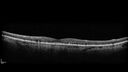

84 year old female The patient had cardiac stents done a week ago. Her stent was done late in the day. She did not notice anything that night but the next morning she noticed that it looked like there was steam coming out of the vent in the ceiling and like there was moister on the mirror. After that her vision changed to look like there was smoke inside her eye. This is more on the left eye than the right eye. Medical Hx: Influenza Immunization Not Received. Pneumococcal Vaccine Not Received. Diabetes Mellitus. Heart attack (2/23/2024). Hypertension, Systemic. Hyperlipidemia. Surgical Hx: Heart Stent (2/23/2024). Hysterectomy. Systemic Meds: Aspirin 81 mg. linaglitin. Metoprolol. NITROGLYCERIN. Ticagrelor. VALSARTAN. VA OD: Dcc20/32 Ncc20/200 VA OS: NccJ16 IOP: TP: OD:11 OS:10

reticular-drusen_119305_052424_03.jpg

Reticular pseudodrusen85 views00000